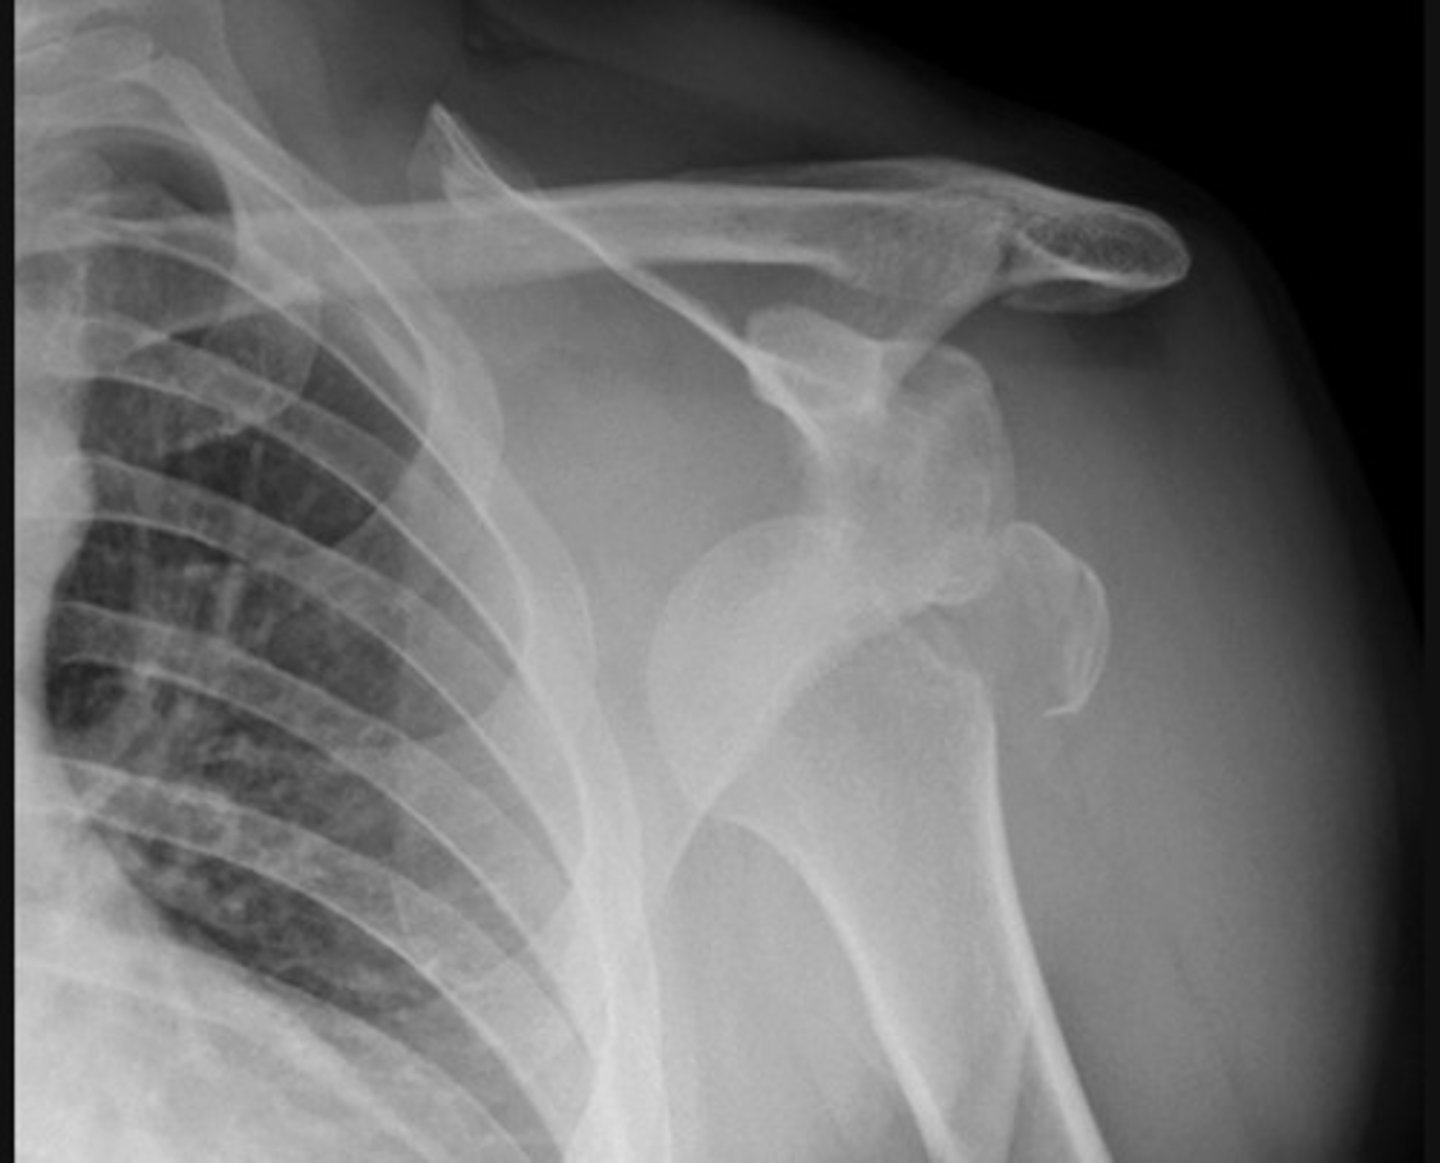

Anterior dislocation. The humeral head is dislocated from the glenoid of the scapula and is now located inferior to the coracoid process of the scapula.

This shoulder anterior dislocation is complicated by a greater tubercle fracture of the humeral head